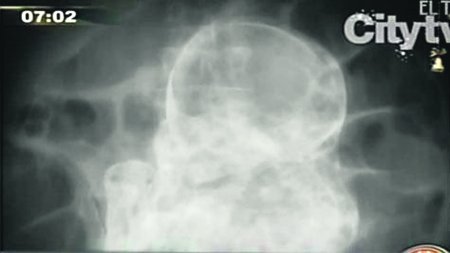

El insólito hecho sucedió en Bogotá, donde una mujer de 84 años de edad fue informada del hallazgo cuando acudió al hospital por problemas estomacales y dolores de cabeza.

La mujer, quien además sufre de demencia senil, llevó al feto por más de 40 años en su vientre. Este caso es conocido como litopedion y puede ser confundido con un tumor ovárico.